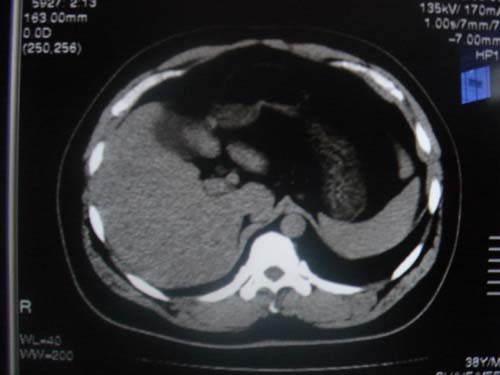

患者 男 40 右上腹不适 有胆囊息肉病史2年

本例就是胆囊比较大,内密度不很均匀,疑有砂砾状结石,未见息肉以及其他异常。

肝脏增大,

最后二副图像示胆囊壁增厚,与肝分界欠清,建议强化ct或磁共振

片中示肝脏的ct值低于脾脏,肝脏右叶外缘部份凹凸不平,考虑脂肪肝,肝硬化可能。结合其检查如b超或ct增强检查。

胆囊未见明显异常,肝脏密度似比脾脏密度低,测量一下ct值排除一下脂肪肝.当然做一下增强或mr就更好了.

肝右叶密度不均,脾大。强烈要求增强扫描除外浸润型肝癌。

肝大   密度降低  脾大  脂肪肝?